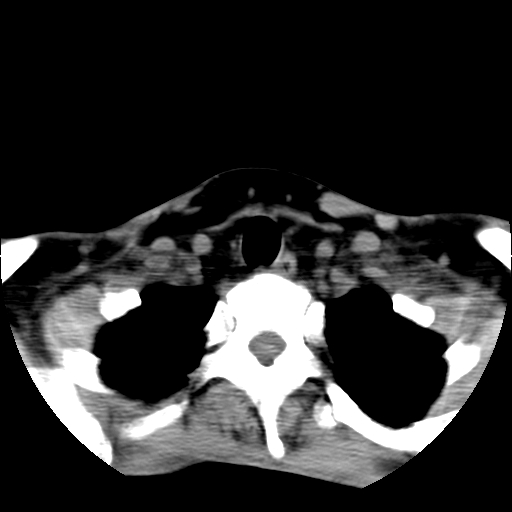

标题: CT24019:男,45岁,发现颈部肿物5个月。 [打印本页]

男,45岁,发现颈部肿物5个月,彩超示:双侧颈部及下颌部软组织增厚。

考虑双侧颈项部良性对称性脂肪增多症。